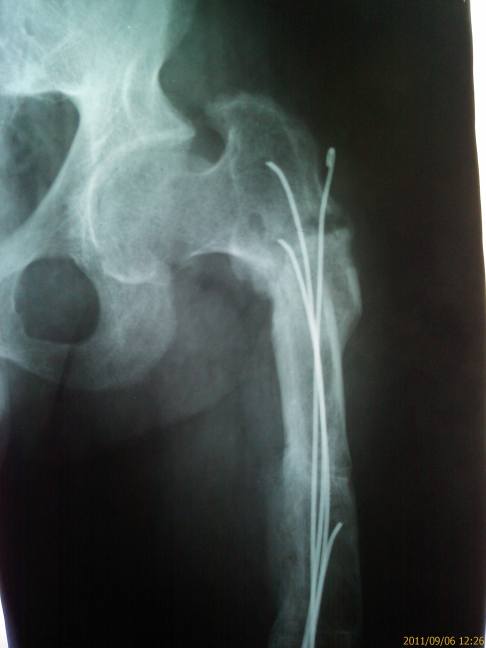

Имя     : Правое бедро.jpg

Тип     : image/jpeg

Размер  : 16054 байтов

Описание: отсутствует

Url     : http://weborto.net:8080/pipermail/ortho/attachments/20110910/89848992/attachment-0004.jpg

В 2007 году рефрактура перелом пластин обеих бедер  в ФГУ "ННИИТО

Росмедтехнологий"  операции    проведены операции  удаление пластин ,

остеосинтез обеих бедренных костей гвоздями Кюнчера. .

Удаление сломанного стержня правой бедренной кости, ресинтез бедра пластиной

с коррегирующей остеотомией  и костной аутопластикой, коррегирующая

остеотомия правой большеберцовой  кости остеосинтез пластиной.  Продолжил

лечение амбулаторно. Иммобилизация 12 недель. .